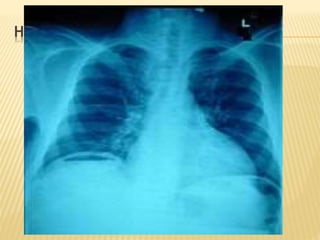

HERE IS YOUR PATIENT’S X-RAY….

PERFORATED PEPTIC ULCER

 Acute abdominal x-ray series

 Lack of free air does NOT rule out perforation